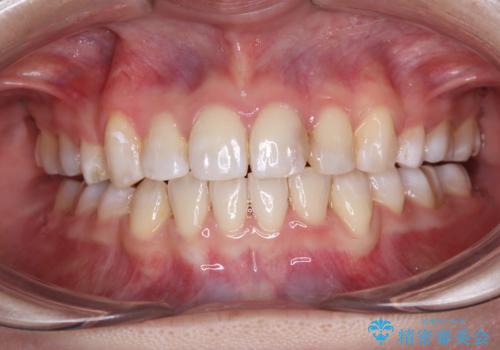

ワイヤー矯正で確実にガタつきを治したい セラミックブラケットによる治療